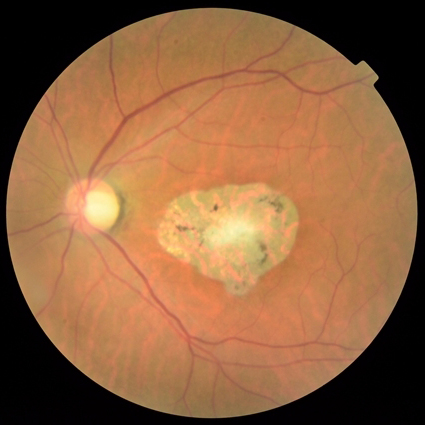

Figure 4: Three CFP fundus images with symptom of GA and corresponding generated images. (a), (b), (c) Original images. (d), (e), (f) Generated images.

Style transferring neural network in [16] was modified to generate new disease images. This network adopts layers from ”conv1 1” to ”conv4 1” in pre-trained VGG-19 [24] network for the encoder, whose weights are provided by ImageNet-pretrained weights. What’s more, multi-level stylization strategy proposed in [16] is applied to optimize the VGG features in different layers. Input images are three CFP images and three FA images as style images shown in Fig. 2 and 5. Six CFP images with three drusen and three GA images in Fig. 3 and Fig. 4. Also, FA images are applied to generate new images in Fig. 6 and Fig. 7. For CFP images, six images are shown in Fig. 3 and in Fig. 4. In Fig. 3, generated images contain round, discrete yellow-white dots, which are the symptom of drusen. In the same way, in Fig. 4, well-demarcated areas appear on the three images. Therefore, style transferring can generate new retinal symptom images.